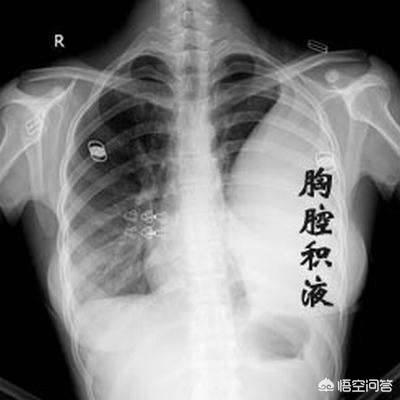

1.呼吸不全は、一般に患者の空気不足として知られ、進行肺癌患者に最も多い。中枢性肺癌では気管や主気管支が閉塞して空気が入りにくくなり、肺の無気肺が大きくなると、次第に息切れや呼吸困難に悩まされるようになる。胸膜転移により大量の胸水が貯留し、肺組織が圧迫されて肺が再開通できなくなる患者もいる。また、肺病変が多すぎて有効呼吸膜面積が著しく減少している患者もいる。これらの理由はすべて、最終的に胸部圧迫感、息切れ、座位呼吸を引き起こし、最終的には呼吸不全に至る。

4.胸水

胸水貯留は肺癌患者によくみられるもう一つの合併症であり、胸水が大量に貯留すると呼吸困難に陥ることがある。

- 肺癌が胸腔に転移すると、胸水、特に血性胸水が貯留することがあり、この時に血を吐くことがある。